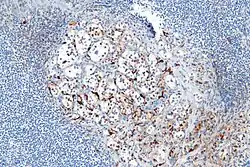

Micrograph highlighting the sustentacular cells in a paraganglioma. S100 immunostain

- About 40% of carcinoids have a scattering of sustentacular cells, which stain positive for S-100.[6]